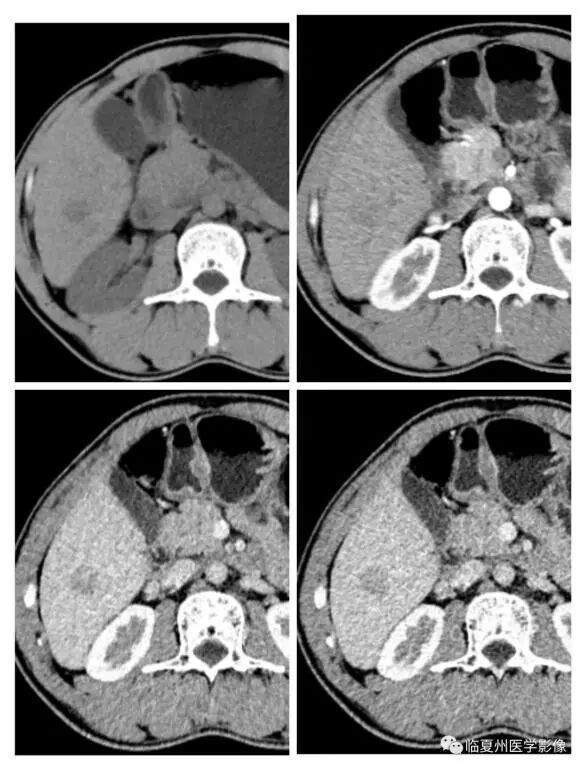

42岁的张先生在做CT检查时,发现肝右叶后下段有一个低密度结节,医生为其做了CT平扫及CT增强检查,只见肝右叶后下段有一枚直径约18毫米的稍低密度灶,定性诊断不明确,无法排除肝癌的可能性。为进一步明确病灶性质,我院磁共振室团队为其实行肝胆特异性造影剂——钆塞酸二钠MRI增强检查,检查后明确诊断为“小肝癌”。目前患者正积极准备行早期根治术。

CT平扫加增强扫描